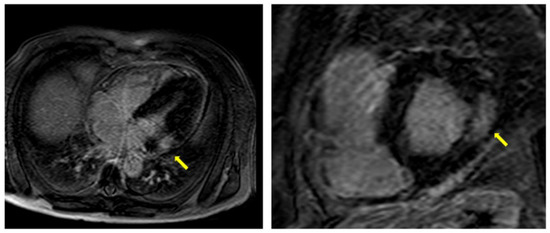

5. Cardiac Magnetic Resonance

- Imbriaco, M.; Pisani, A.; Spinelli, L.; Cuocolo, A.; Messalli, G.; Capuano, E.; Marmo, M.; Liuzzi, R.; Visciano, B.; Cianciaruso, B.; et al. Effects of enzyme-replacement therapy in patients with Anderson-Fabry disease: A prospective long-term cardiac magnetic resonance imaging study. Heart 2009, 95, 1103–1107. [Google Scholar] [CrossRef]

- Deva, D.P.; Hanneman, K.; Li, Q.; Ng, M.Y.; Wasim, S.; Morel, C.; Iwanochko, R.M.; Thavendiranathan, P.; Crean, A.M. Cardiovascular magnetic resonance demonstration of the spectrum of morphological phenotypes and patterns of myocardial scarring in Anderson-fabry disease. J. Cardiovasc. Magn. Reson. 2016, 18, 14. [Google Scholar] [CrossRef] [PubMed]

| Cine-sequences | -Measurement of LV mass, ventricular volumes, LV and RV EF, wall motion assessment | -Better quantification of LV papillary muscle mass |

| LGE | -Fibrosis usually localized at mid-wall in the basal infero-lateral area of LV -Very extensive and diffuse in advanced AFD | -Suggestive of AFD when in the typical localization -Additionally present in patients without LVH -Strongly correlated with more CV events |